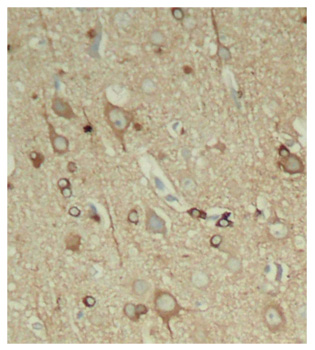

• AP0163: image 2

Immunohistochemical analysis of paraffin-embedded rat hippocampal region tissue from a model with Alzheimer, using phospho-MAPT-S396 antibody.